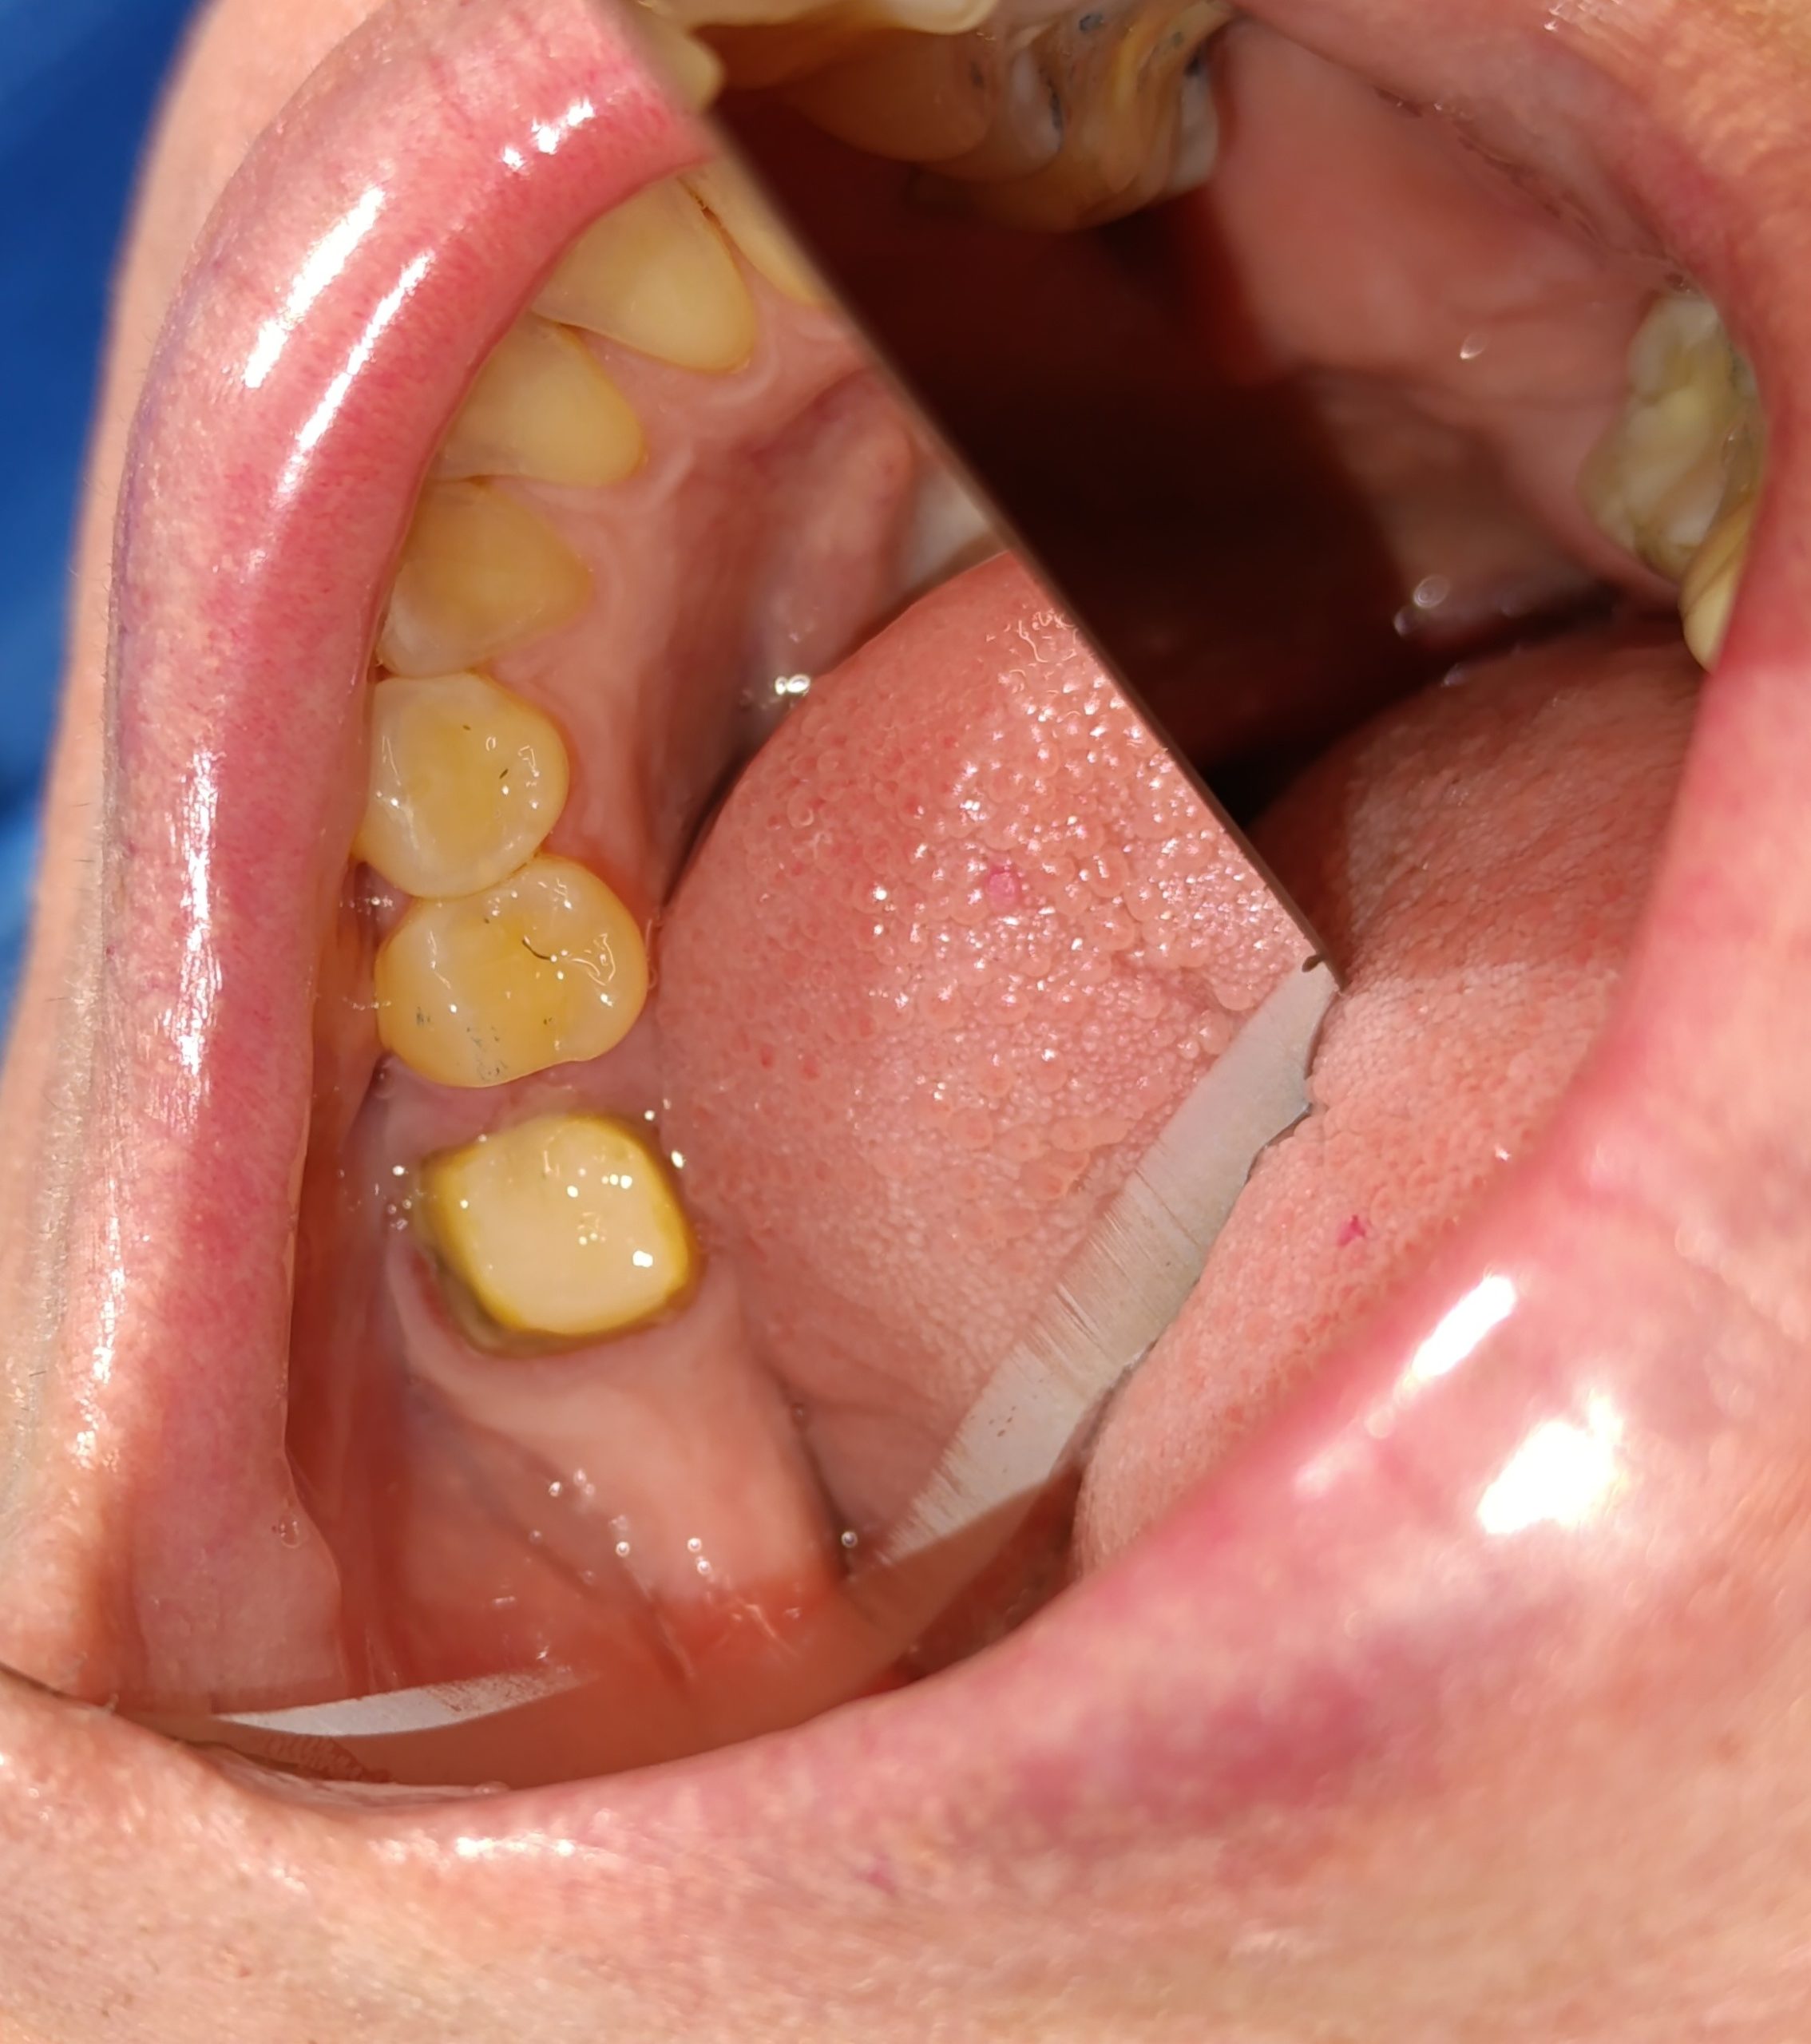

Αρχική κλινική εικόνα του μεγάλου οδοντικού ελλείμματος

Τελική κλινική εικόνα του ολοκεραμικού επένθετου στο γομφίο